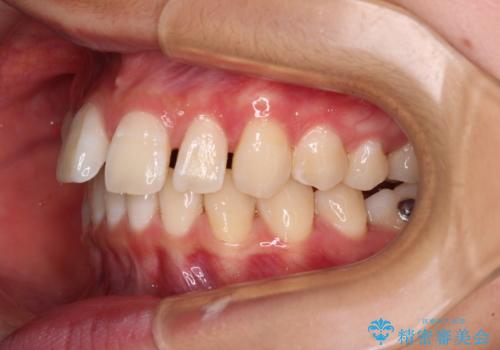

深い咬み合わせで前方に煽られた前歯 高校生のインビザライン矯正治療

- 前歯の隙間と前方に飛び出していることを気にして来院された患者様です。

奥歯の咬み合わせを見ると、上顎が下顎に対して相対的に前方にありました。

咬み合わせも深くなっていたため、上顎臼歯を後方に移動させつつ、下顎の小臼歯を直立させ、奥歯の咬み合わせを改善する必要があります。